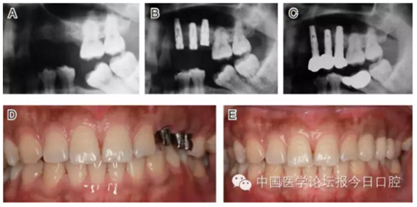

病例8 多顆種植體植入(圖10)

圖10